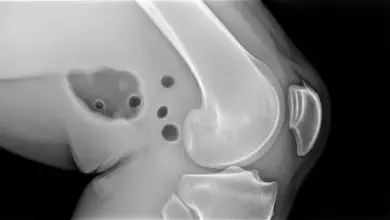

O edema ao redor de um ligamento representa acúmulo de líquido e alteração inflamatória nos tecidos vizinhos, que pode aparecer após torções, impactos, movimentos bruscos ou sobrecarga repetitiva.

Em alguns casos, o ligamento permanece íntegro e o edema reflete apenas uma agressão local. Em outros, o exame pode estar mostrando a repercussão de uma lesão parcial ou completa.

Depois disso, a ressonância ajuda a detalhar as estruturas envolvidas. Radiografias também podem ser indicadas, principalmente quando há trauma importante, dor persistente ou suspeita de lesão óssea associada.